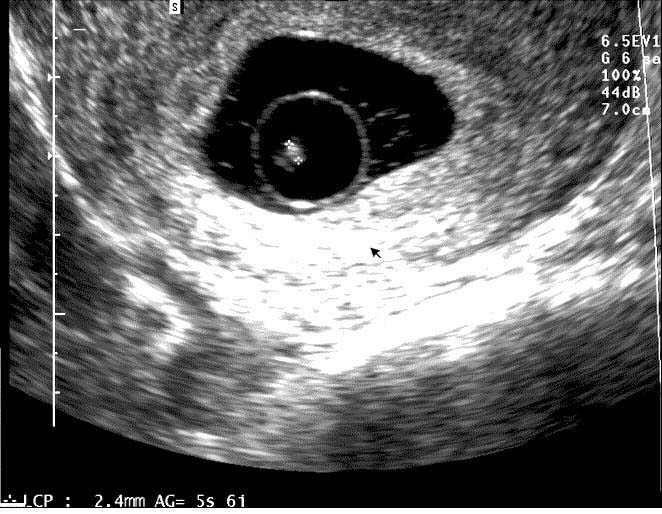

Эмбрион 6 7 Недель ФотоВыберите Ваш пол👨 👉🏻👉🏻👉🏻МУЖЧИНА👈🏻👈🏻👈🏻👩🦱 👉🏻👉🏻👉🏻ЖЕНЩИНА👈🏻👈🏻👈🏻Эмбрион 6 7 Недель Фото (132 фото)